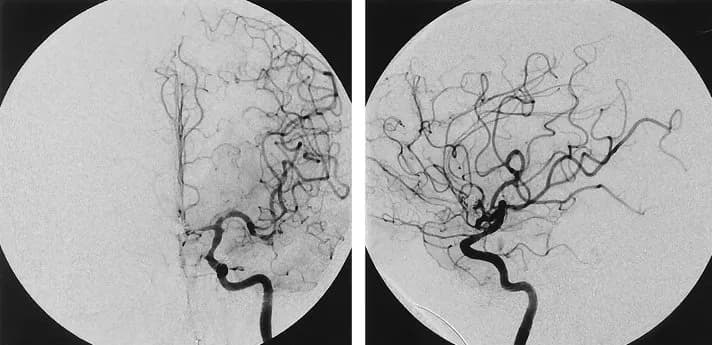

Ứng dụng của chụp mạch số hóa xóa nền (DSA) trong tim mạch

Kỹ thuật chụp mạch số hóa xóa nền (DSA) trong tim mạch

Giới thiệu:

Trong lĩnh vực tim mạch, can thiệp nội mạch ngày càn...